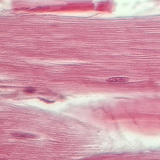

Ampliação 800x

Biologia